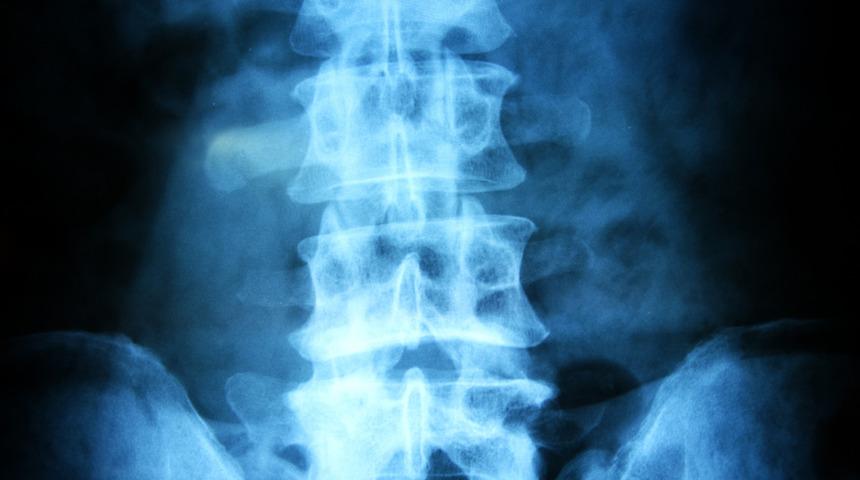

Bel fıtığı operasyonlarında felç kalma riski yok!

Bel fıtığı uygun bir şekilde tedavi edildiğinde yüz güldürücü sonuçlar ortaya çıkmaktadır. Beyin, Sinir ve Omurilik Cerrahisi Uzmanı Doç. Dr. Ahmet Yıldızhan, bel fıtığı operasyonlarında felç kalma riskine ve ameliyatın detaylarına değindi.

Yapılan araştırmalara göre bel fıtığı hastalarının az bir kısmı ameliyata ihtiyaç duymaktadır. Bel fıtığı konusundaki en büyük yanlışlardan birisi ameliyat sonucunda felç kalma riski olduğudur. Ancak deneyimli ekibimizle ciltten itibaren mikroteknik kullanarak yaptığımız bel fıtığı ameliyatlarında felç kalma riski bulunmamaktadır. Hatta birçok bel fıtığı hatası yeni yöntemler ile ameliyat olduktan sonra aynı gün içinde yürüyüp ertesi gün taburcu olmaktadırlar. Gelişmiş cerrahi aletler ile gerçekleştirilen operasyonlar hastaların hem ameliyat sürecini hem de ameliyat sonrasını konforlu bir şekilde atlatmalarını sağlamaktadır.

Bel fıtığı ameliyatları son derece dar bir alanda ve sinirlerin yoğun bulunduğu bir sahada gerçekleştirilmektedir. Ancak ameliyat sırasında kullanılan üstün yöntemler sayesinde ameliyat bölgesi daha da büyütülmektedir. Bu da cerrahın daha kibar, temiz ve emniyetli bir şekilde çalışmasını sağlamaktadır. 1,5-2 santimetre büyüklüğündeki minik kesiden ciltten itibaren mikroteknik kullanılarak gerçekleştirilmektedir.